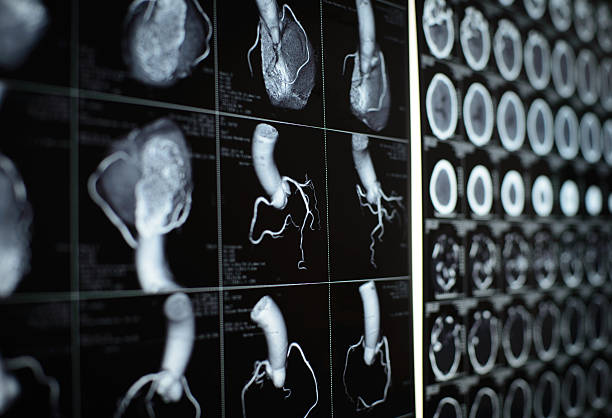

협심증은 심장의 혈액 공급이 감소하여 심장 근육에 산소와 영양분 공급이 충분하지 않아 발생하는 증상입니다. 이는 일반적으로 심장 동맥의 협착으로 인해 발생합니다. 이번 시간에는 협심증에 대해 보다 자세히 알고 초기 대응이 중요한 협심증이기 때문에 협심증의 초기 증상에 대해 자세히 정리해보도록 하겠습니다.

협심증은 심장 질환의 일종으로, 심장 근육에 충분한 혈액 공급이 이루어지지 않아서 발생합니다. 이는 심장근육에 손상을 일으키고, 심부전, 심근경색, 심부전 등의 심각한 합병증을 유발할 수 있습니다. 따라서 협심증 초기에 대응하지 않으면, 심장근육에 손상을 일으키고 이로 인해 심각한 합병증이 발생할 가능성이 높아집니다.